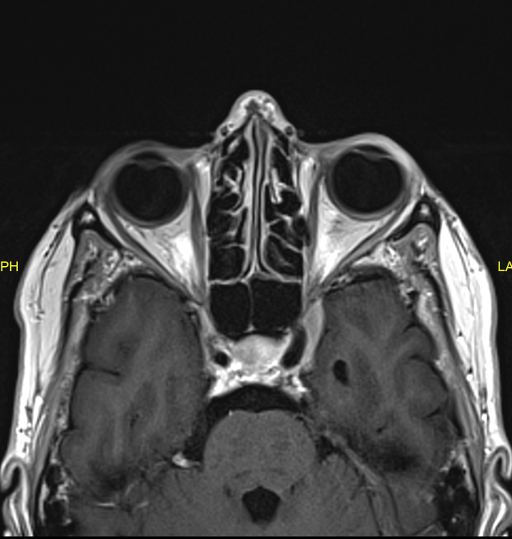

A 57-year-old Caucasian woman presented to our department in April 2014 with sudden binocular horizontal diplopia. There were no other neurological symptoms, no recent infection or trauma. Apart from a refractive procedure (LASIK) years before, she had no ophthalmological history. Medical history consisted of migraine and hypercholesterolemia for which she was taking Atorvastatin 10 mg. No other cardiovascular risk factors could be withheld. She fulfilled an administrative occupation at the time. On ocular examination there was an esotropia (ET) of 10° of the right eye (RE) and an abnormal head turn to the right side. Eye motility exam showed a –4 abduction limitation of the RE due to a complete right sixth nerve palsy. There was no nystagmus. Alternate cover testing (ACT) showed 45 Δ ET with right fixation (RF) and 15 Δ ET with left fixation (LF) at 30 cm, and 45 Δ ET and 18 Δ ET respectively at 6 m. Best corrected visual acuity (BCVA) as measured with EDTRS chart was 1.0 in both eyes (BE). Intra-ocular pressure (IOP) was normal. Pupils were equal and reactive to light. Eyelids were symmetrical; there was no eyelid retraction or ptosis. Clinical corneal reflex testing revealed a hypoesthetic cornea on the left side. Apart from this, anterior and posterior segment findings were normal. Blood pressure was normal. Laboratory analysis revealed no abnormalities: blood cell count was normal, liver and renal function test were normal, serology (including syphilis and Borrelia burgdorferi) was negative, as was antibody testing (ANCA, ANA, anti-phospholipids, IgG). The patient was sent for further neurological investigation, but aside from the sixth nerve palsy the neurological exam including lumbar puncture appeared normal. Magnetic resonance imaging (MRI) without gadolinium contrast of the brain and orbit showed a small incidental lesion (7x10 mm) (Figure 1 [Fig. 1]) in the right lateral ventricle (DD astrocytoma, hamartoma, subependymoma), not responsible for the right sixth nerve palsy. This lesion remained unchanged during follow-up with gadolinium-enhanced MRI scans 6 and 12 months later.

Figure 1: MRI scan (2014) showing lesion right lateral ventricle